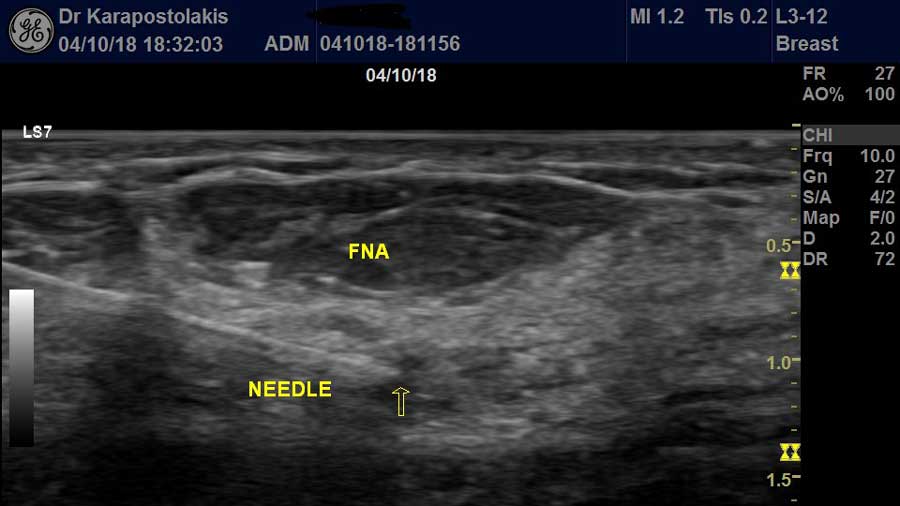

Διενεργούνται στο Ιατρείο Υπερήχων FNA -παρακεντήσεις με λεπτή βελόνη- με υπερηχογραφική καθοδήγηση σε παιδιά, εφήβους και ενήλικες:

- Όζων Θυρεοειδούς Αδένα

- Μορφώματα Σιελογόνων Αδένων (παρωτίδα, υπογνάθιος αδένας)

- Μορφώματα Μαστού

- Λεμφαδένων

- Δερματικά Ογκίδια

Μετά την παρακέντηση ο εξεταζόμενος μπορεί να επιστρέψει στις δραστηριότητες του άμεσα χωρίς κανένα πρόβλημα.

Οι απαντήσεις των παρακεντήσεων δίνονται αυθημερόν από διεθνούς φήμης κυτταρολόγο ώστε να μην παρατείνεται περαιτέρω η αγωνία του εξεταζόμενου.